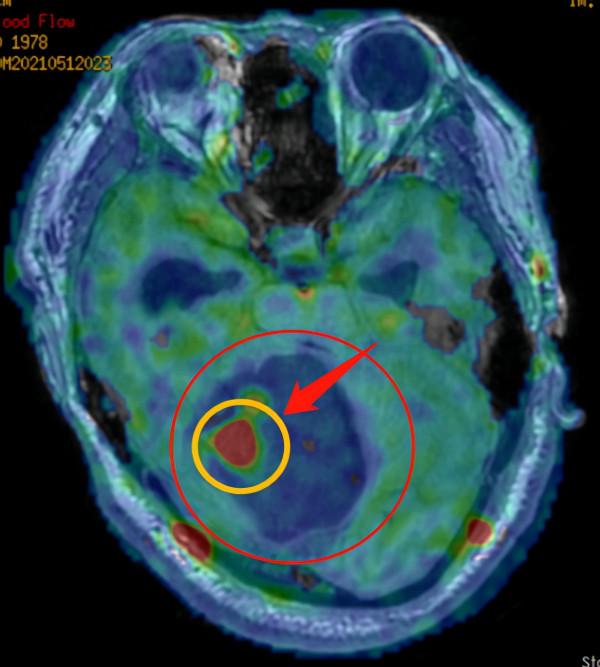

影像檢查顯示:右側小腦巨大囊實性佔位,形似“戒指”。

根據患者的病史及影像檢查資料,穆林森分析,患者走路時的“醉酒”症狀是因為小腦處長了腫瘤,並懷疑他顱內的腫瘤是血管母細胞瘤。

“它的內部大部分是液體,像是裝滿水的氣球,在一端的結節才是罪魁禍首。只要找到並切除了結節,其他看似很大的部分,也就不足為懼了。”穆林森形象地比喻道:“這個腫瘤形狀看起來確實像‘戒指’,它看著雖大,其實只有那個‘發亮的寶石’才是手術切除的關鍵。至於其它部分,就像是‘紙老虎’,一捅就破。”

術後病理提示為血管母細胞瘤。穆林森解析,血管母細胞瘤是一種真性血管性良性腫瘤,又稱為血管網織細胞瘤或者成血管細胞瘤,起源於中胚葉細胞的胚胎殘餘組織。該病多發於小腦半球,部分患者在脊髓中也會出現。顱腦血管母細胞瘤患者可能會出現頭痛、頭暈,有時還會出現噁心、嘔吐、行走不穩等症狀。

穆林森介紹,血管母細胞瘤分為囊性和實性兩種。本例患者就是較為典型的囊性血管母細胞瘤。該類腫瘤常在增強CT或磁共振上呈現“戒指”樣結構,存在一個明顯增強的結節;而實性腫瘤則整體呈現高訊號。“對於血管母細胞瘤,手術切除是首選治療辦法,絕大部分患者可以取得良好的預後。”穆林森補充道。